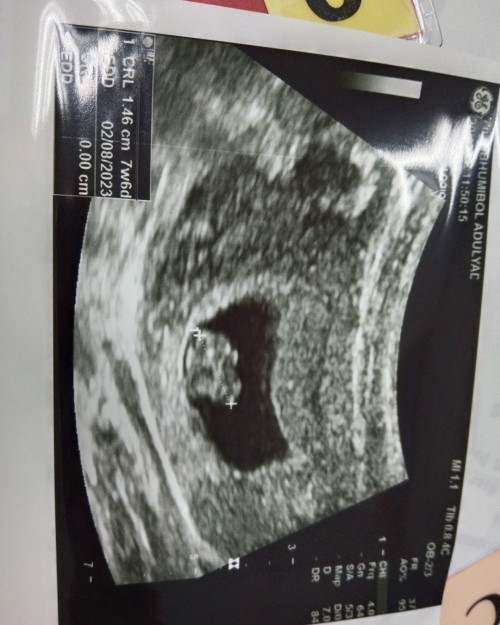

7w+3d